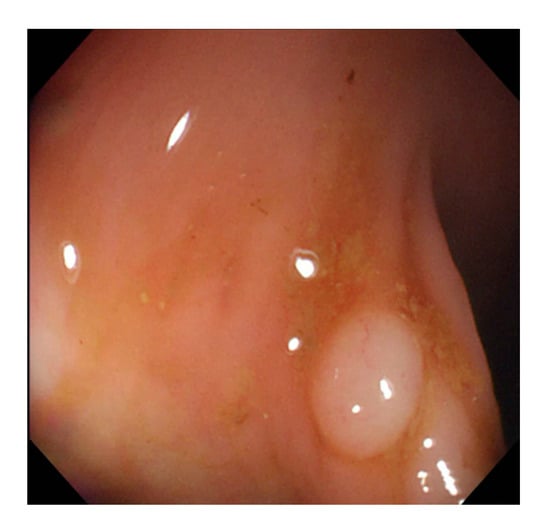

Currently, many medical images are processed into grayscale images, such as ultrasound, computed tomography (CT), and magnetic resonance (MR) images. Tan et al. [44] applied a gray-level cooccurrence matrix and CNN to CT images for polyp diagnosis. Zhang et al. [45] compress the three-channel color images of chest CT to grayscale images. A five-layer deep CNN with stochastic pooling is used to diagnose chest-based COVID-19. Xie et al. [46] mentioned that in deep learning, colors are not the key features influencing accurate image classification. They also discovered that in X-ray image classification, the speed and accuracy of processing grayscale images were considerably higher than those of processing RGB images. The grayscale method used was ITU-R Recommendation BT.601 [47]. Moreover, misjudgments were easily made in the presence of excessive intestinal wall textures, when polyps were too small (Figure 2), and when polyp textures were similar (Figure 3) to intestinal wall textures.

Figure 2.

Excessive intestinal wall textures with small polyps.